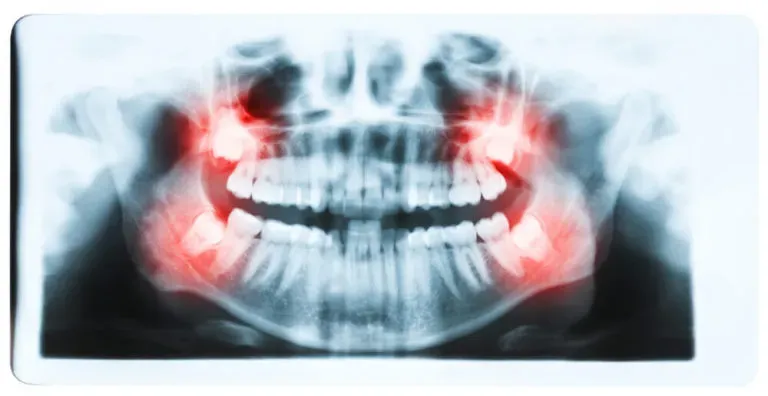

Ósemki, znane jako zęby mądrości, mogą powodować różne problemy zdrowotne, które wpływają na komfort i zdrowie jamy ustnej. Jednym z najczęstszych problemów jest impakcja, która występuje, gdy ząb nie ma wystarczającej przestrzeni, aby prawidłowo się wyrżnąć. To może prowadzić do bólu, obrzęku i dyskomfortu w okolicy szczęki. Dodatkowo, zęby mądrości mogą być narażone na infekcje, jeśli nie są w stanie się prawidłowo wyrzynać, co może prowadzić do poważniejszych problemów zdrowotnych, takich jak ropnie.

Innym problemem związanym z ósemkami jest przesunięcie innych zębów w łuku zębowym, co może prowadzić do zgryzu i estetyki uśmiechu. W przypadku, gdy ósemki zaczynają się wyrzynać, mogą wywierać nacisk na sąsiednie zęby, co skutkuje ich przesunięciem. W związku z tym, wielu stomatologów zaleca usunięcie ósemek, aby uniknąć potencjalnych komplikacji. Regularne wizyty u dentysty mogą pomóc w monitorowaniu stanu zdrowia zębów mądrości i wczesnym wykrywaniu problemów, co jest kluczowe dla zachowania zdrowia jamy ustnej.Typowe powikłania związane z wyrzynaniem się ósemek

Wyrzynanie się ósemek może prowadzić do szeregu powikłań zdrowotnych. Najczęściej występującym problemem jest ból, który może być intensywny i długotrwały, zwłaszcza gdy ząb nie ma wystarczającej przestrzeni do prawidłowego wyrznięcia. Ponadto, infekcje są powszechnym skutkiem nieprawidłowego wyrzynania się ósemek, co może prowadzić do powstawania ropni i zapalenia dziąseł. Wiele osób doświadcza również przesunięcia zębów, które może wpływać na zgryz oraz estetykę uśmiechu. Te problemy zdrowotne wskazują na potrzebę regularnych kontroli stomatologicznych, aby monitorować stan zębów mądrości i podejmować odpowiednie działania w razie potrzeby.